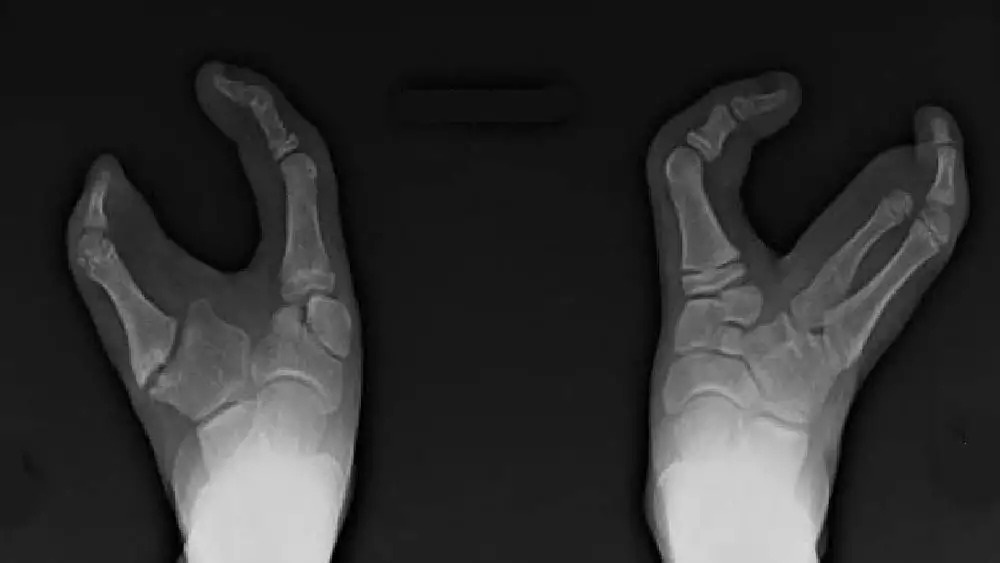

জিনগত কারণেই এই উপজাতি গোষ্ঠীতে জন্ম নেয়া প্রতি চার জন শিশুর এক জনের পায়ের আঙুল দুইটি। তাদের পায়ে বৃদ্ধাঙ্গুষ্ঠ এবং কনিষ্ঠা বাদে মাঝের তিনটি আঙুল অনুপস্থিত। ভাদোমা উপজাতির মানুষদের যে দুইটি আঙুল আছে, সেগুলোও ভেতর দিকে ঢোকানো। পায়ের আকৃতি অনেকটা উটপাখি বা অস্ট্রিচের মতো। তাই অনেকেই তাদের ‘অস্ট্রিচ পদবিশিষ্ট’ উপজাতি বলে থাকেন।

শারীরিক এই প্রতিবন্ধকতা থাকা সত্ত্বেও ভাদোমা উপজাতির মানুষেরা নিজেদের প্রতিবন্ধী বলে মনে করেন না। তারা মনে করেন পায়ের আঙুলের এই ধরনের গঠন হওয়ার ফলে তারা দ্রুত এবং মসৃণ উপায়ে গাছে উঠতে পারেন। ভাদোমা উপজাতির প্রতিটি মানুষ ‘লবস্টার ক্ল সিনড্রোম’ নামক এক জিনগত রোগে আক্রান্ত। এই রোগে আক্রান্ত মানুষদের জন্মসূত্রেই পায়ে এক বা একাধিক আঙুল থাকে না।